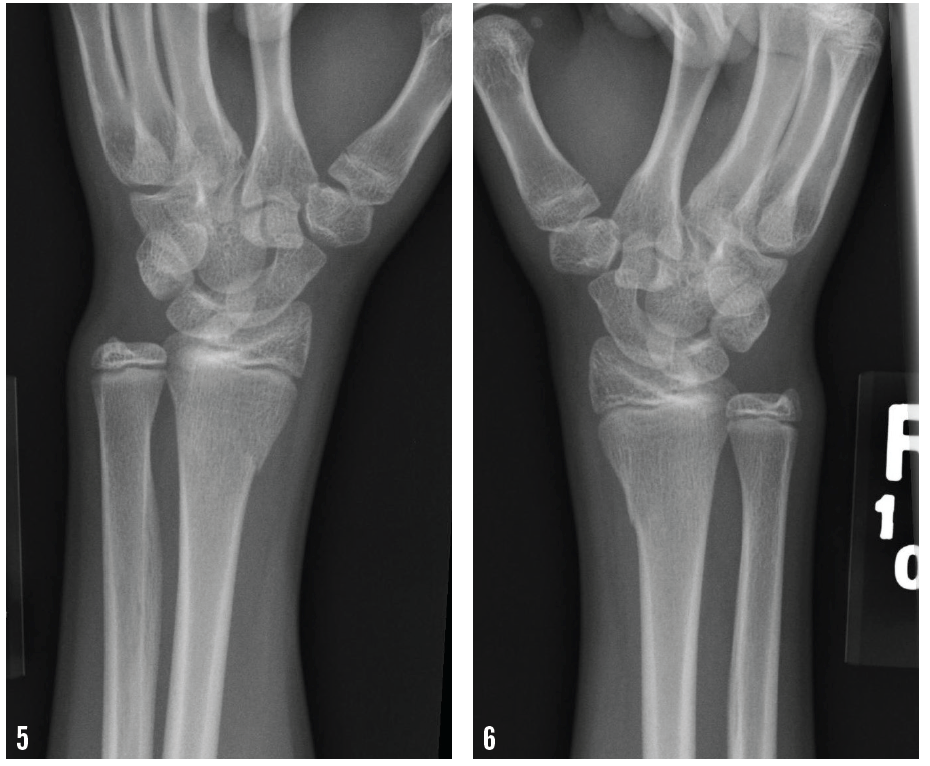

Anteroposterior radiographs are shown below.

Wrist radiographs revealed bilateral transverse fractures of both distal radii, with slight apex dorsal angulation on the right side (Figures 1-6). Both sides showed normal mineralization and slight age-appropriate openings at the epiphyses.